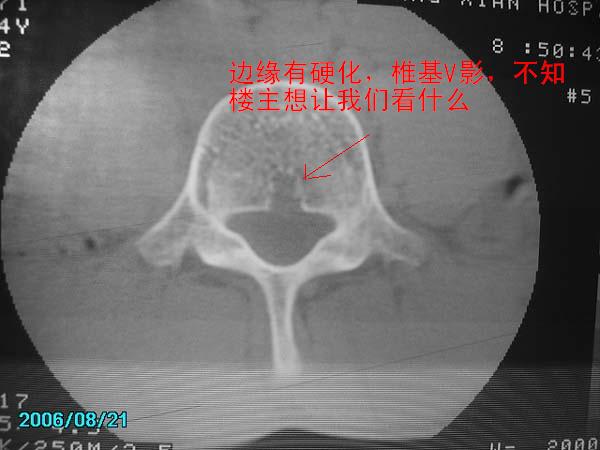

除有第3-5腰椎椎体后缘中央血管沟显示外,诸椎间盘比较正常。我也象13081830109战友那样看见了指纹,呵呵。

以下是引用守望可可西里在2006-11-13 22:44:00的发言:[br][br]  除有第3-5腰椎椎体后缘中央血管沟显示外,诸椎间盘比较正常。我也象13081830109战友那样看见了指纹,呵呵。